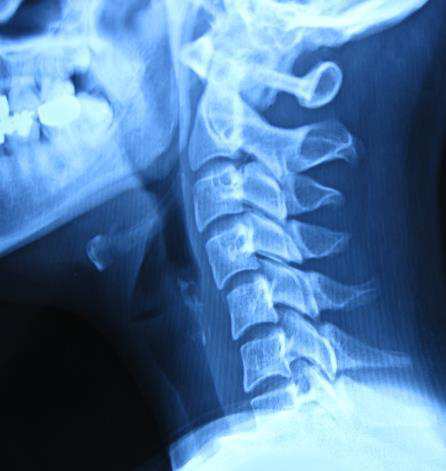

카이로프랙틱이나 추나요법에서의 키포인트는 상부경추입니다. 이 상부경추는 척추를 바로 잡는 열쇠 역할을 합니다. 다른 부분을 아무리 잘 교정해도 상부경추가 교정되지 않으면 척추 교정이 쉽지 않습니다. 문제는 상부경추의 교정 테크닉이 쉽지 않기 때문에 시술자의 숙련도나 이해 정도가 많이 요구되는 부분입니다.